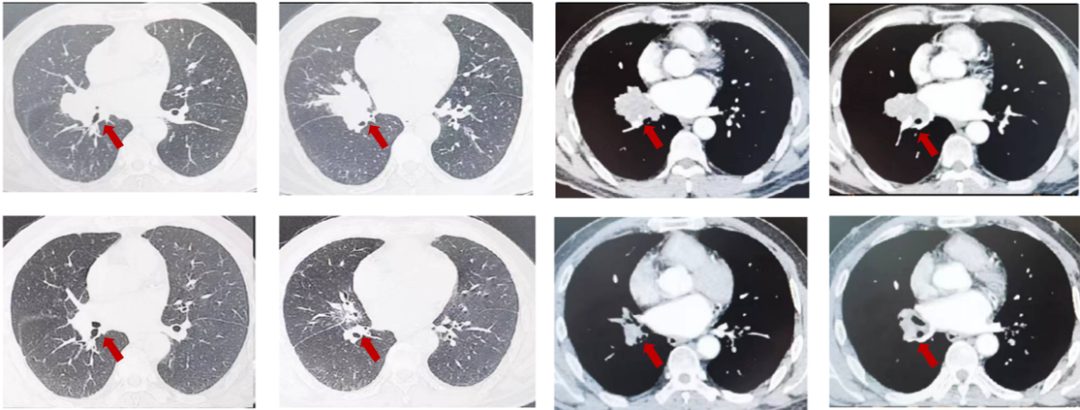

患者王XX,男,54岁,2023年4月以“咳嗽1个月”入院,PS1分,高血压3年,行替米沙坦40毫克日1次口服血压控制好,否认冠心病,糖尿病等病史,吸烟史:吸烟30年,每天20支。肺CT(外院,2023-3):右肺中叶肿物,32mm*37mm,边缘见分叶,纵隔淋巴结肿大,右肺中叶中心型肺癌?邻近上叶前段局部受累不除外。右肺中叶炎症。双肺气肿、肺大泡。肝脏多发小囊肿。支气管镜:右肺中叶见新生物,表面有坏死物附着,堵塞管腔,取病理。病理:鳞癌。PD-L1(DAKO 22C3)(+,CPS=20)。cT2bN2M0,ⅢA期。经MDT讨论后,患者为可切除手术患者,建议新辅助治疗。给予患者3周期特瑞普利单抗+紫杉醇/卡铂治疗,3周期评效PR。

图3:由上至下分别展示基线(A.)及免疫化学治疗后改变(B.)。红色箭头指示病灶位置,由左至右分别为右肺肿物肺窗、右肺肿物纵隔窗。